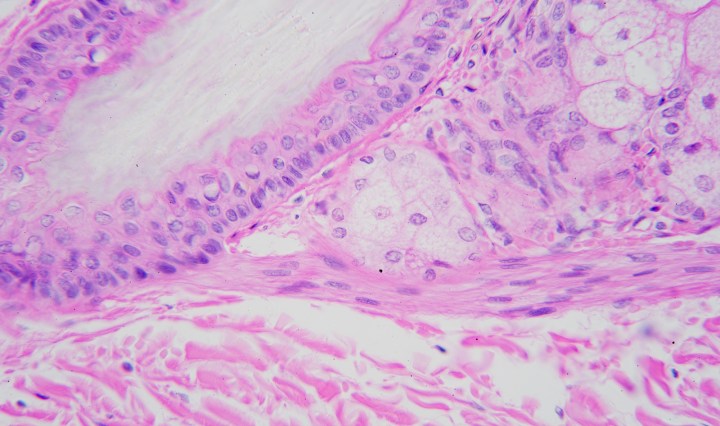

Gastro-esophageal junction

August 21, 2016September 16, 2016 Kit Ng

The connection between the lower esophagus and the stomach cardia is known as the gastro-esophageal junction or esophagogastric junction.  Histologically this is the transition between the stratified squamous epithelium from the esophagus to the simple columnar epithelium of the stomach. Continue reading Gastro-esophageal junction